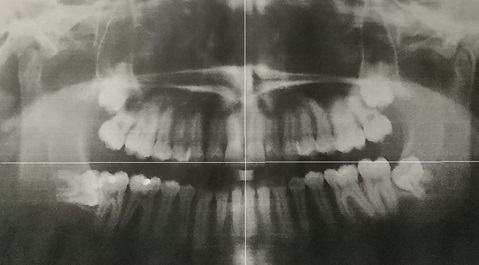

下顎の解剖図

下顎の位置

顎関節嚙み合わせ

上顎と下顎/嚙み合わせ

正中の不一致

「頭蓋骨と顎の連動性」

緑色の箇所は下顎がうまる所であります

下顎頭(かがくとう)

側頭骨がずれるだけでも上顎が連動して

いるのでかみ合わせなども異なるのが

分かります。ゆえに、頭蓋骨のバランス

が崩れると緑の位置が下顎頭がずれるの

で顎の位置が変化することによって

かみ合わせが変化します。左の写真は

検査で普段気になる場所がそこにあるの

で触ってしまいがちですが触ると余計

に変化していきます

顎関節の違和感にに関しては触るという行為

は当院ではなるべく避ける事を提案しております